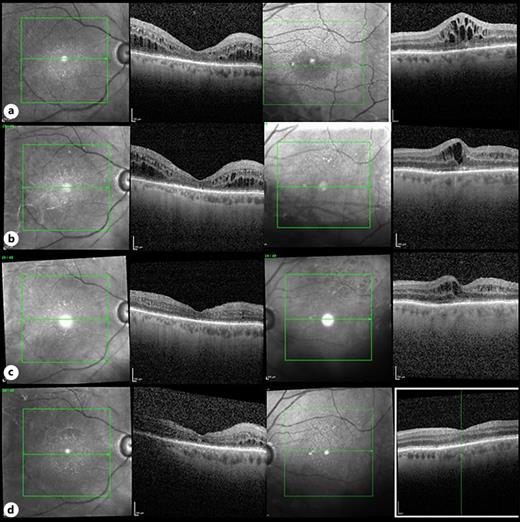

Bilateral Cystoid Macular Edema with Zanubrutinib Therapy A Case Case Reports In Oncology Karger 1 have you got everything? Case reports in oncology | karger publishers. Goblet cell adenocarcinoma (gca) of the appendix is an uncommon type of cancer that includes both. Oncology | case reports in oncology | karger publishers. Added 14 december 2009 • updated 4 april 2024. Download our quick checklist before starting. Regarding positive outcomes, there is one prospective trial. Case Reports In Oncology Karger.